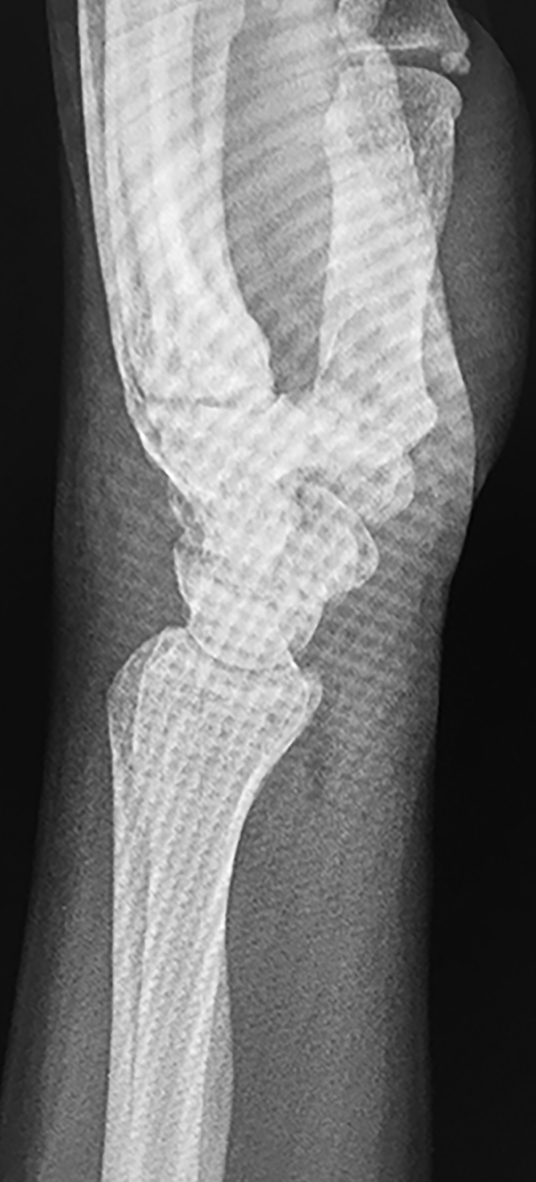

Figura 3: Caso 9

a) Radiografia de perfil pre-opertaoria

b) TC pre-operatoria. Corte sagital

c) TC pre-operatoria. Corte coronal

d) Radiografías post-operatorias

e) Radiografía de frente, 33 meses seguimiento, pseuodartrosis persistente

f) Radiografía de frente, 33 meses seguimiento, pseuodartrosis persistente